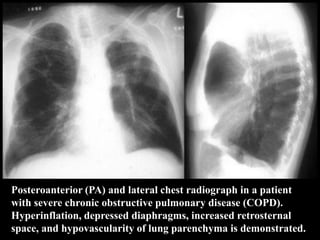

Posteroanterior (PA) and lateral chest radiograph in a patient

with severe chronic obstructive pulmonary disease (COPD).

Hyperinflation, depressed diaphragms, increased retrosternal

space, and hypovascularity of lung parenchyma is demonstrated.